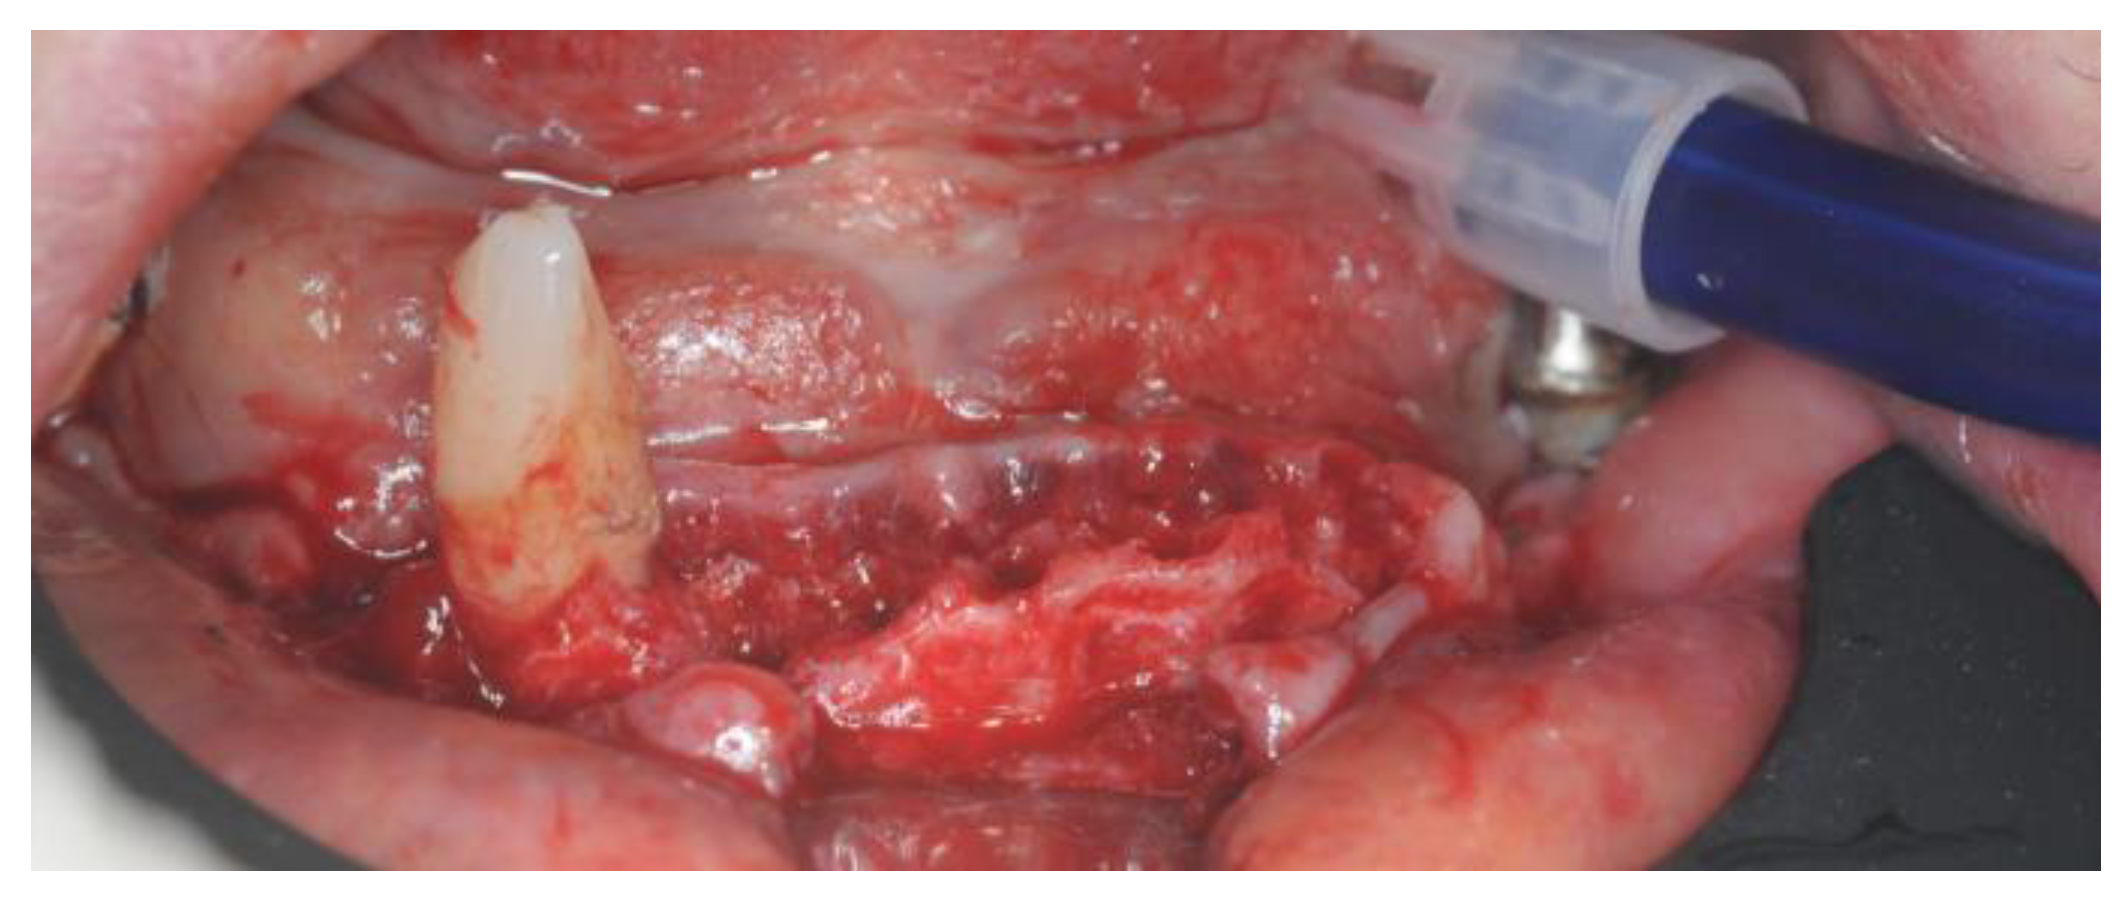

2.4. Surgery